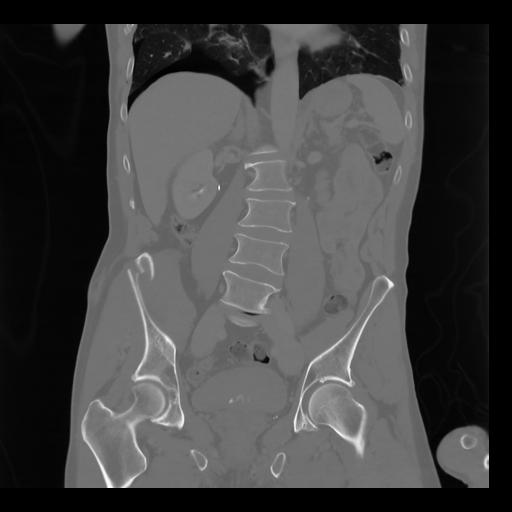

35 CUERPO,CE,Coronal,3.000,CUERPO,Coronal,